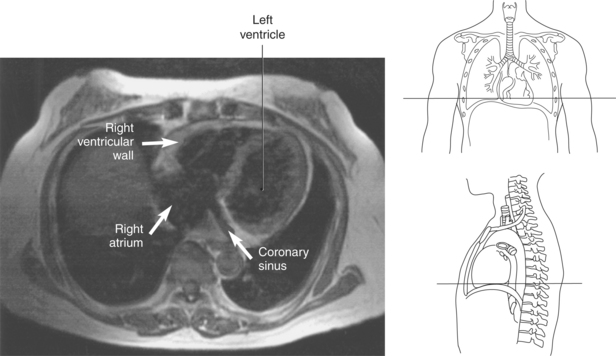

The right atrium forms the right border of the heart and receives deoxygenated blood from the body via the superior and inferior venae cavae and from the coronary sinus and cardiac veins that drain the myocardium. A small muscular embryonic appendage, the right auricle, projects upward and toward the left from the right atrium, covering the root of the aorta (Figure 6.40). The right ventricle lies on the diaphragm and comprises the largest portion of the anterior surface of the heart. It receives deoxygenated blood from the right atrium and forces it into the pulmonary trunk for conveyance to the lungs. Projecting off the inferior surface of the ventricular walls are conical-shaped projections of cardiac muscle called papillary muscles that anchor the cusps of the tricuspid valve to the right ventricle (Figure 6.39). The left atrium lies posterior to the right atrium and is the most posterior surface of the heart. It also has an embryonic appendage, the left auricle, that projects to the left of the pulmonary trunk over the superior surface of the heart. The left atrium receives oxygenated blood directly from the lungs via the four pulmonary veins (two on each side). The left ventricle forms the apex, left border, and most of the inferior surface of the heart. It receives oxygenated blood from the left atrium and pumps it into the aorta for distribution throughout the systemic circuit. The myocardium of the left ventricle is normally three times thicker than that of the right ventricle, reflecting the force necessary to pump blood to the distant sites of the systemic circulation (Figures 6.41 through 6.52). Two papillary muscles project from the ventricular walls to anchor the bicuspid valve to the ventricle (Figures 6.39 and 6.47).

Figure 6.43 Axial, T1-weighted MR scan of left atrium.

Key: RV, Right ventricle; LV, left ventricle; LA, left atrium; RA, right atrium.

Most of the venous return from the heart is carried by the coronary sinus as it runs along the posterior section of the coronary sulcus and terminates in the right atrium immediately to the left of the inferior vena cava. The coronary sinus is a wide venous channel situated in the posterior part of the coronary sulcus and is the main vein of the heart (Figures 6.100 through 6.102). Its tributaries include the great, small, and middle cardiac veins; the left posterior ventricular vein; and the oblique vein of the left atrium. The great cardiac vein, the main tributary of the coronary sinus, arises near the apex of the heart and ascends in the anterior interventricular groove along with the anterior interventricular artery to the base of the ventricles. It receives blood from the left posterior ventricular vein and the left marginal vein before emptying into the coronary sinus. The small (right) cardiac vein runs in the coronary sulcus between the right atrium and ventricle and joins the coronary sinus from the right side. It receives blood from the right atrium and ventricle. The middle (posterior) cardiac vein commences at the apex of the heart and ascends along the posterior interventricular groove to the base of the heart, where it drains into the coronary sinus near the drainage site of the small cardiac vein. It receives blood from the posterior surface of both ventricles. The left posterior ventricular vein carries blood from the posterior wall of the left ventricle as it runs along the diaphragmatic surface of the left ventricle to drain into either the great cardiac vein or the coronary sinus. The oblique vein of the left atrium, a small vessel, descends obliquely over the posterior wall of the left atrium and enters the left end of the coronary sinus. Two small anterior cardiac veins drain directly into the right atrium (Figure 6.100).